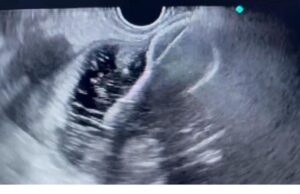

ಮಣಿಪಾಲ, 23 ಜುಲೈ 2024: ಗಮನಾರ್ಹವಾದ ವೈದ್ಯಕೀಯ ಪ್ರಗತಿಯಲ್ಲಿ, ಮಣಿಪಾಲದ ಕಸ್ತೂರ್ಬಾ ಆಸ್ಪತ್ರೆಯು ಎಂಡೋಲ್ಟ್ರಾಸೌಂಡ್-ಗೈಡೆಡ್ ಗ್ಯಾಸ್ಟ್ರೋಜೆಜುನೋಸ್ಟೊಮಿ (EUS-GJ) ಎಂದು ಕರೆಯಲ್ಪಡುವ ನವೀನ ಎಂಡೋಸ್ಕೋಪಿಕ್ ವಿಧಾನವನ್ನು ಯಶಸ್ವಿಯಾಗಿ ನಿರ್ವಹಿಸಿದೆ. ಹಿರಿಯ ವಯಸ್ಸಿನ ವ್ಯಕ್ತಿಯೊಬ್ಬರಿಗೆ ಈ ವಿಧಾನವನ್ನು ನಡೆಸಲಾಯಿತು, ಅವರು ತೀವ್ರ ತೆರನಾದ ಗ್ಯಾಸ್ಟ್ರಿಕ್ ಔಟ್ಲೆಟ್ ಅಡಚಣೆಯಿಂದ ಬಳಲುತ್ತಿದ್ದರು, ಇದರಿಂದಾಗಿ ಅವರಿಗೆ ಆಹಾರ ಸೇವಿಸಲು ಸಾಧ್ಯವಾಗುತ್ತಿರಲಿಲ್ಲ.

ಗ್ಯಾಸ್ಟ್ರೋಎಂಟರಾಲಜಿ ಮತ್ತು ಹೆಪಟಾಲಜಿಯ ಪ್ರಾಧ್ಯಾಪಕರಾದ ಡಾ.ಶಿರನ್ ಶೆಟ್ಟಿ ನೇತೃತ್ವದ ವೈದ್ಯಕೀಯ ತಂಡವು ಕನಿಷ್ಟ ಅರಿವಳಿಕೆಯಲ್ಲಿ ಈ ಅತ್ಯಾಧುನಿಕ ವಿಧಾನವನ್ನು ಕೈಗೊಳ್ಳಲು ನಿರ್ಧರಿಸಿತು . ಇದು ಜಪಾನಿನ ಎಂಡೋಸ್ಕೋಪಿಸ್ಟ್ಗಳ ಆವಿಷ್ಕಾರವಾಗಿದೆ . ಈ ಕಾರ್ಯವಿಧಾನದ ಮೂಲಕ ಹೊಟ್ಟೆಯನ್ನು ಸಣ್ಣ ಕರುಳಿಗೆ ಸಂಪರ್ಕಿಸಲು ಸಾದ್ಯವಾಗತ್ತದೆ, ಇದರಿಂದಾಗಿ ಆಹಾರ ಸೇವಿಸಲು ಇದ್ದ ಅಡಚಣೆಯನ್ನು ತಪ್ಪಿಸಲಾಗುತ್ತದೆ ಮತ್ತು ರೋಗಿಯು ಮೌಖಿಕವಾಗಿ ಆಹಾರವನ್ನು ತೆಗೆದುಕೊಳ್ಳಲು ಅನುವು ಮಾಡಿಕೊಡುತ್ತದೆ ಎಂದು ಡಾ.ಶಿರನ್ ಶೆಟ್ಟಿ ವಿವರಿಸಿದ್ದಾರೆ.